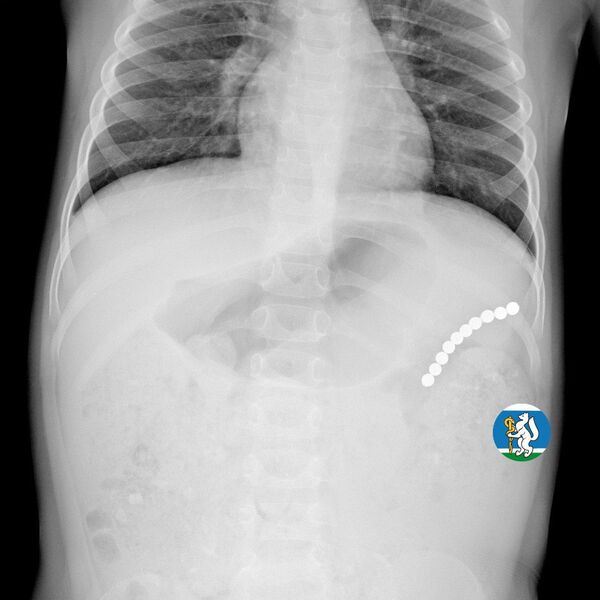

Девочка рассказала родителям о плохом самочувствии, и те показали ее врачам. Медики направили пациентку на рентген грудной клетки. Благодаря обследованию специалисты обнаружили в проекции желудка цепочку магнитов, соединенных между собой. Ребенку сразу же госпитализировали и оказали помощь.

«Для минимизации риска осложнений удаление инородных тел было проведено интраоперационно. В ходе вмешательства дежурная бригада врачей извлекла 10 магнитных шариков, цепочка которых в длину составила 5 сантиметров», — рассказал детский хирург ДГКБ №9 Андрей Чукреев.